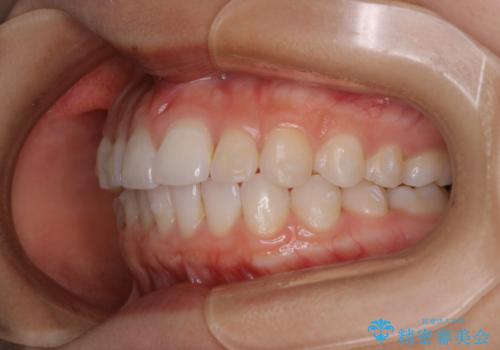

前歯のがたつきをインビザラインで治療

- 上下前歯のがたつきが気になるとの事で来院された患者様です。がたつきの程度が軽度であったため、インビザラインライトにて治療をおこないました。

がたつきの程度が軽度であったことと、インビザラインを正しく装着して頂けたことで短期間で治療終了することが出来ました。